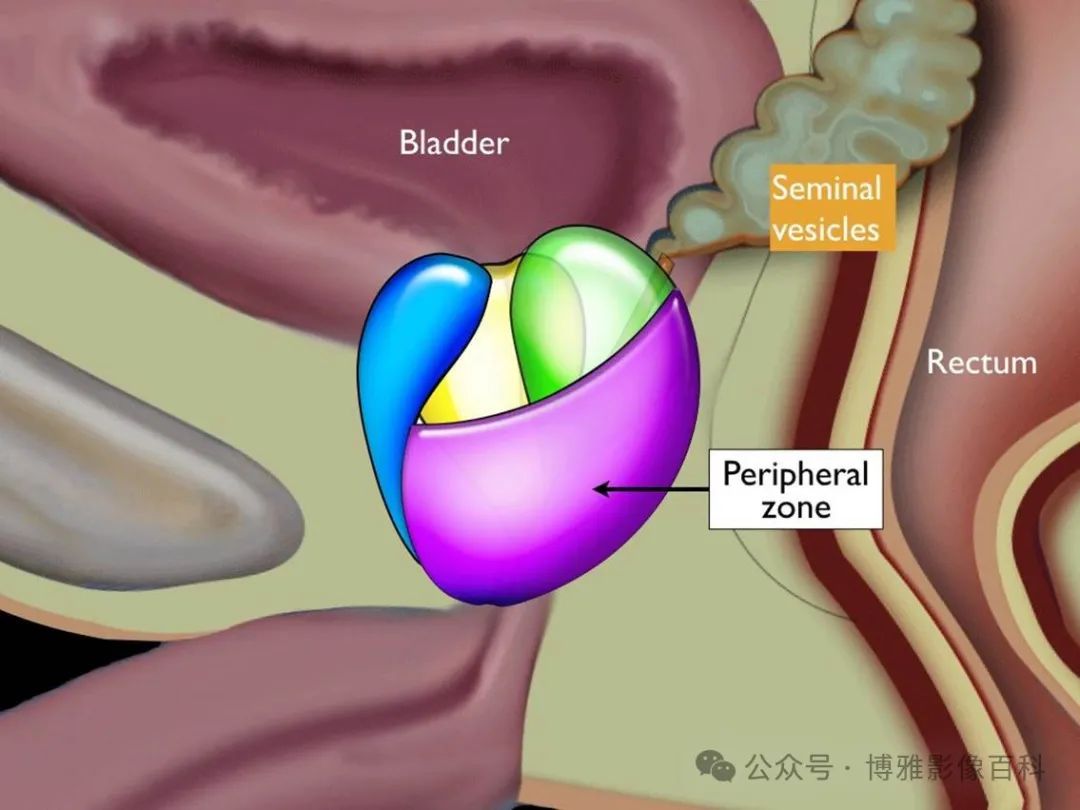

前列腺分区解剖学

70-75% 的前列腺癌起源于外周带 (PZ)。该区域的后部可以通过直肠指检进行检查。